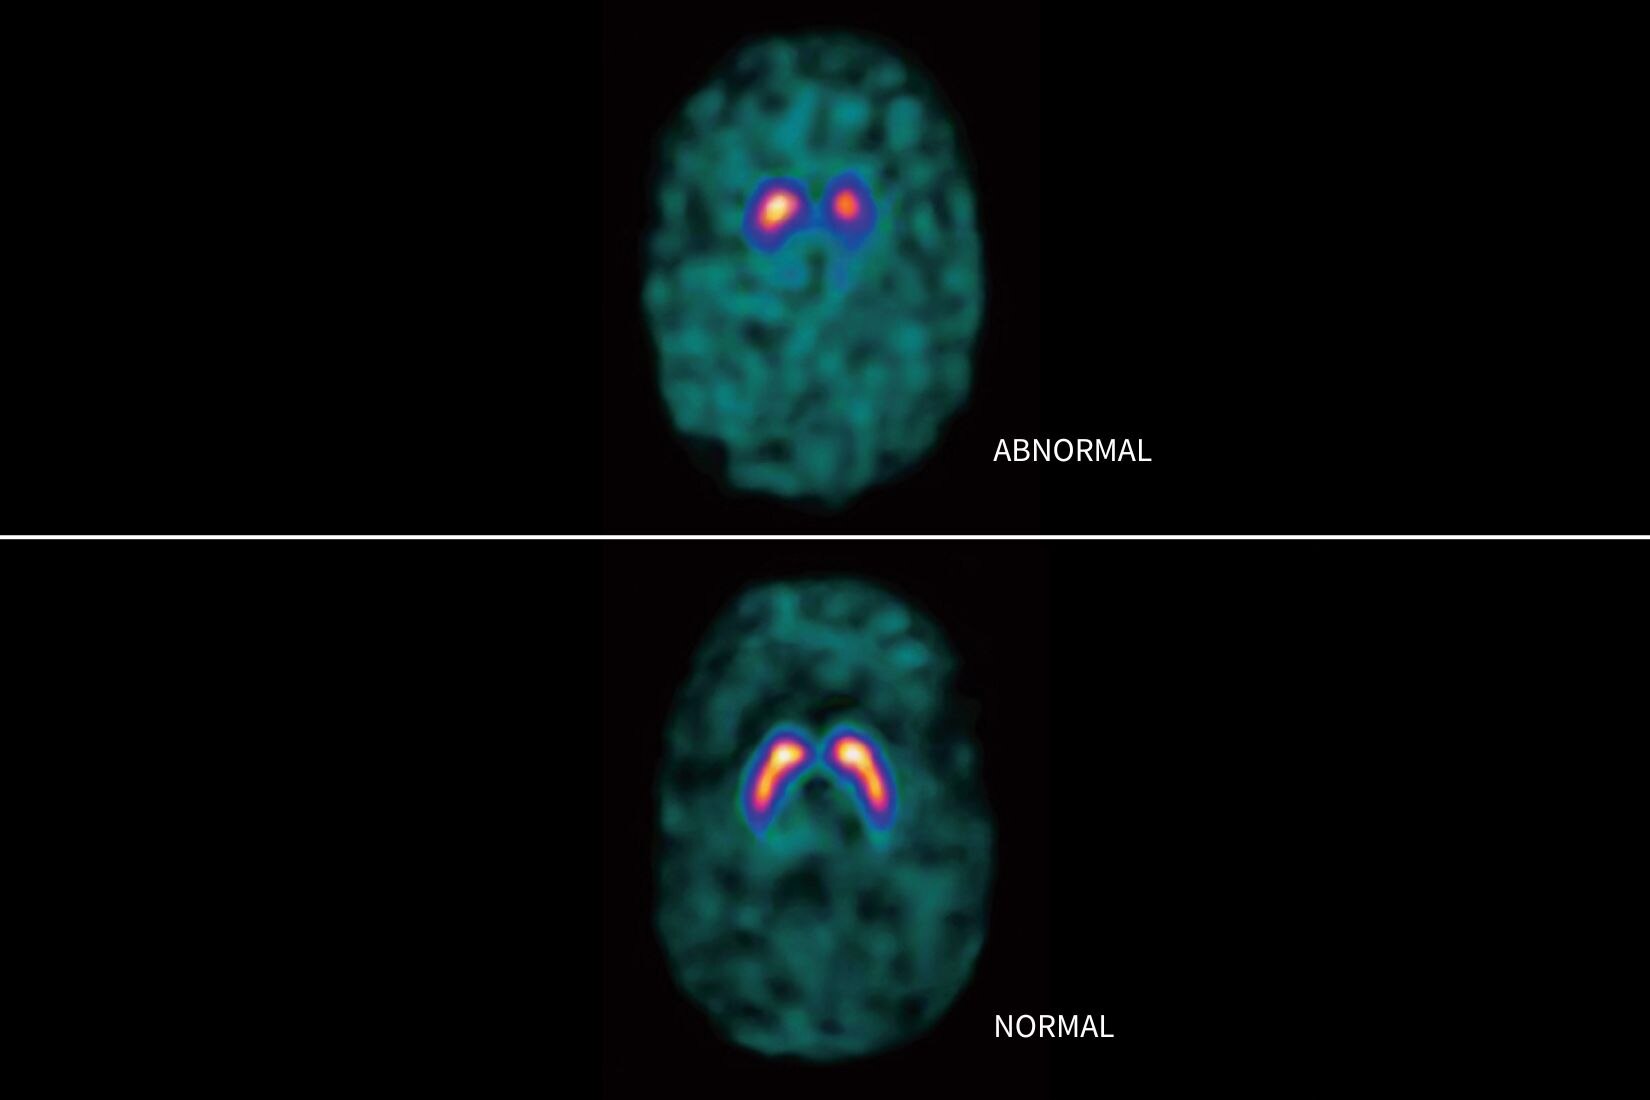

Cuantificación del calcio automatizada basada en el aprendizaje profundo

• El modelo de aprendizaje profundo etiqueta automáticamente los territorios de las arterias coronarias.

• El modelo de aprendizaje profundo segmenta automáticamente las calcificaciones dentro de los territorios de las arterias coronarias y proporciona cuantificaciones totales y por territorio.

• Los modelos de aprendizaje profundo se han desarrollado y entrenado utilizando una amplia variedad de conjuntos de datos clínicos de un grupo de población global, abarcando varios tipos de escáneres y proveedores.

• Capacidad para asignar las calcificaciones a ramas de arterias coronarias individuales.

• Capacidad para cuantificar y etiquetar las calcificaciones encontradas en la aorta y en las válvulas cardíacas.